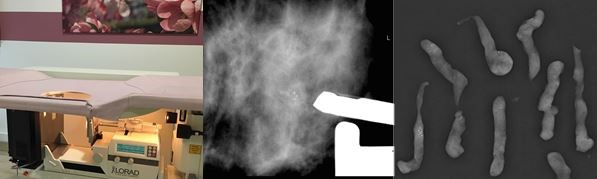

Sie liegen dafür in Bauchlage auf einer Liegevorrichtung mit Mammographie-Gerät (Abb. unten links). Der zu untersuchende Bereich der Brust wird leicht komprimiert. Mittels Mammographie-Aufnahmen der auffälligen Region werden die Veränderungen in der Brust aufgesucht und die Biopsie am Computer geplant. Nach gründlicher Desinfektion der Haut und lokaler Betäubung wird die Biopsienadel computergestützt platziert. Anschließend werden Gewebeproben zielgenau entnommen (Abb. unten Mitte). Die Entnahmestelle wird mit einem kleinen Metallclip (Titanclip) markiert. Im Falle von abklärungsbedürftigen Mikroverkalkungen erfolgt unmittelbar nach der Biopsie eine Röntgenkontrolle der entnommenen Proben um nachzuweisen, dass eine relevante Menge Kalk entfernt wurde (Abb. unten rechts). Der Eingriff dauert ca. 30 Minuten. Nach einer Beobachtungszeit von ca. 60 Minuten wird eine Kontrollmammographie angefertigt und ein Kompressionsverband angelegt, danach können Sie nach Hause gehen. Die entnommenen Gewebeproben werden im Institut für Pathologie des Universitätsklinikums Düsseldorf untersucht.